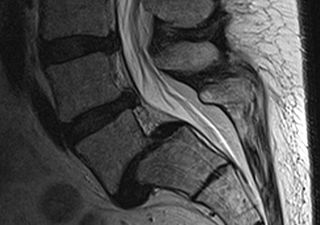

Spondylolisthesis is a condition in which the affected vertebra slips on the adjacent vertebra below it. It is very commonly seen at L5 and S1 vertebra level. It is more commonly seen in females than males. The most probable cause is due to congenital abnormality in the development of the neural arch. The pain usually starts after an injury and the symptoms are rare before adolescence.

Slip in Spondylolisthesis is measured by measuring the anterior slip of vertebral body. Meyerding classified the slip into 4 grades:-